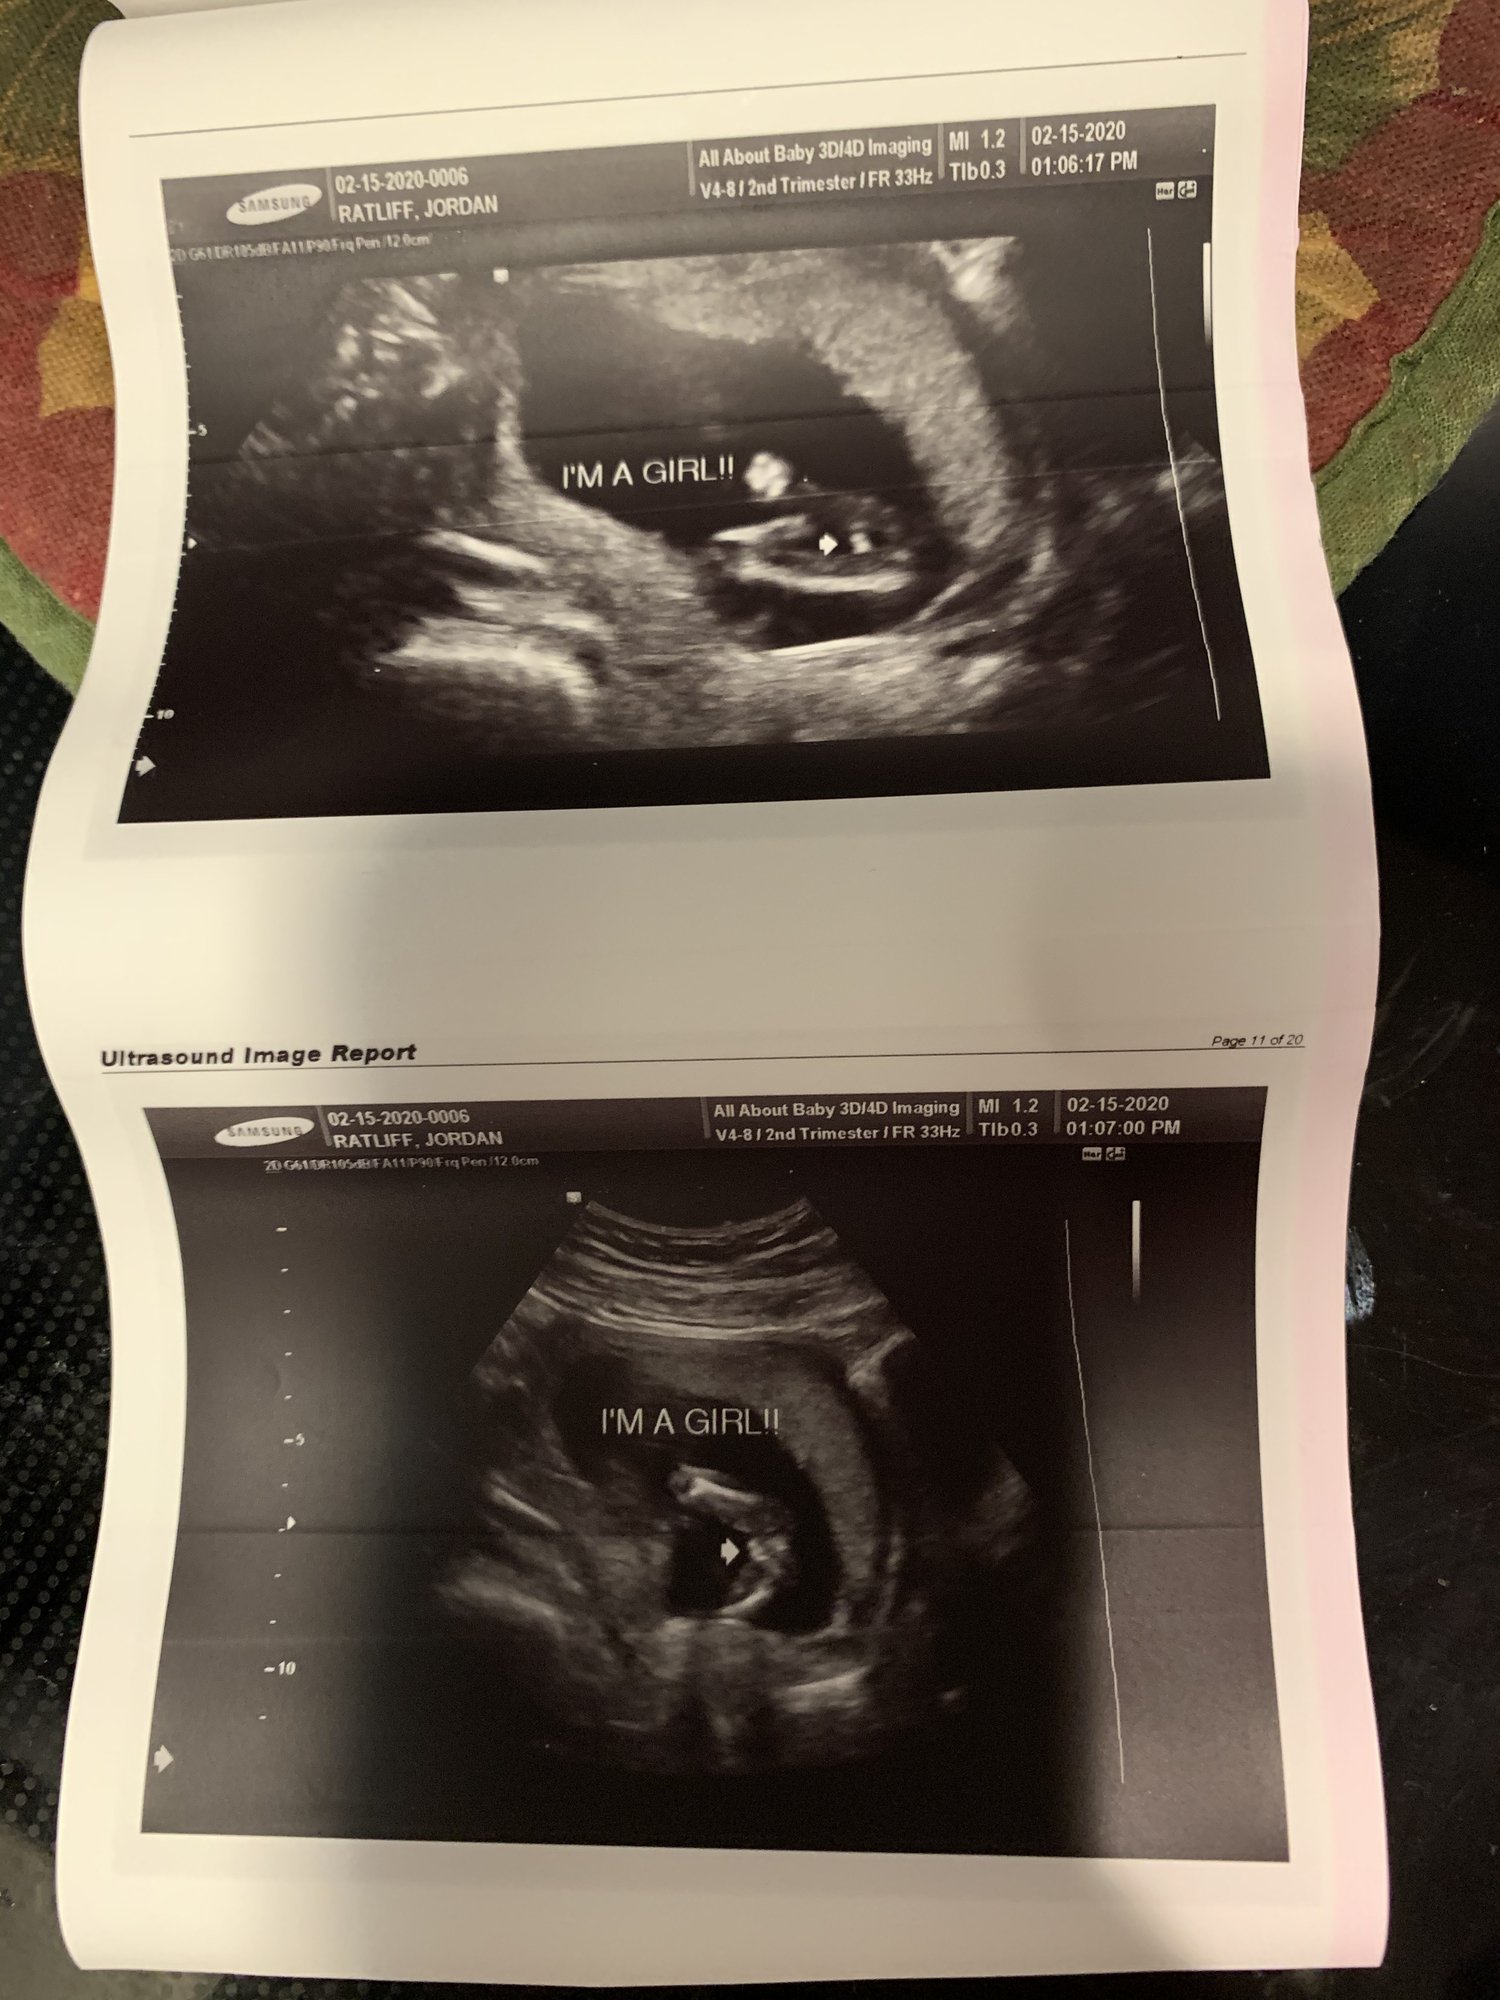

We just got our results back today on Valentines Day ❤️ And It’s A Girl🎀 I’m so excited my husband doesn’t know yet we are having gender reveal today for him and the kids so he will find out then